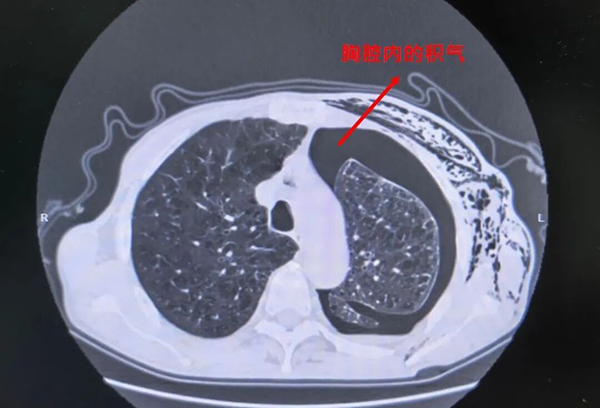

2025年底,他因气胸复发

在当地医院接受“胸腔闭式引流术”治疗

气胸竟迟迟无法复张

“患者肺功能基础差,经长时间胸腔闭式引流仍持续漏气,临床诊断为难治性气胸。这是一种特殊类型的‘支气管胸膜瘘’,瘘口不愈导致病情反复,必须精准定位、对症施治。”

术后复查显示,李老伯气胸明显吸收,漏气量显著减少,肺部复张态势良好。

(复查CT显示肺部复张良好,完成使命的海绵被取出)